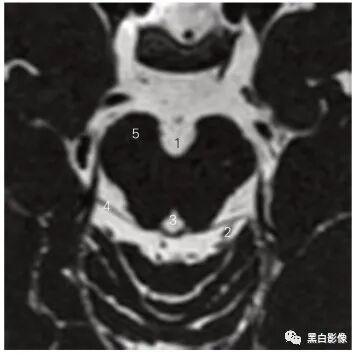

图5-11 经舌咽神经、迷走神经和副神经的3D-CISS序列斜冠状断层MR图像

1 脑干 brain stem

2 舌咽神经、迷走神经和副神经 glossopharyngeal, vagus and accessory nerves

3 颈静脉孔 jugular foramen 4 小脑 cerebellum